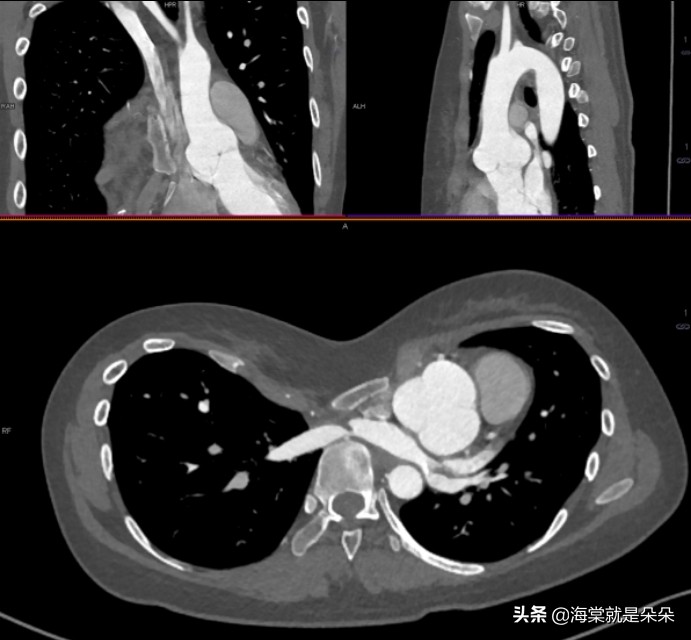

国际上评估漏斗胸的畸形指数,普遍使

用 Haller指数,关于漏斗最深点到脊柱前方距离、胸骨最凹陷处层面胸廓的最大横径。

正常人的 HI 平均指数是 2.52,漏斗胸患者则超过 3.2,大于 3.5 为重度漏斗胸,3.25 到 3.5 为中度,小于 3.25 为轻度。

这个女孩20岁才来就诊,Haller指数达到了16!胸骨体都快贴到胸椎了!心脏大血管受压迫移到左边,主动脉窦膨大!

她是体检超声怀疑主动脉瘤的,吓哭了。但是这个漏斗胸确实已经发展到影响器官发育和功能了。需要做手术。